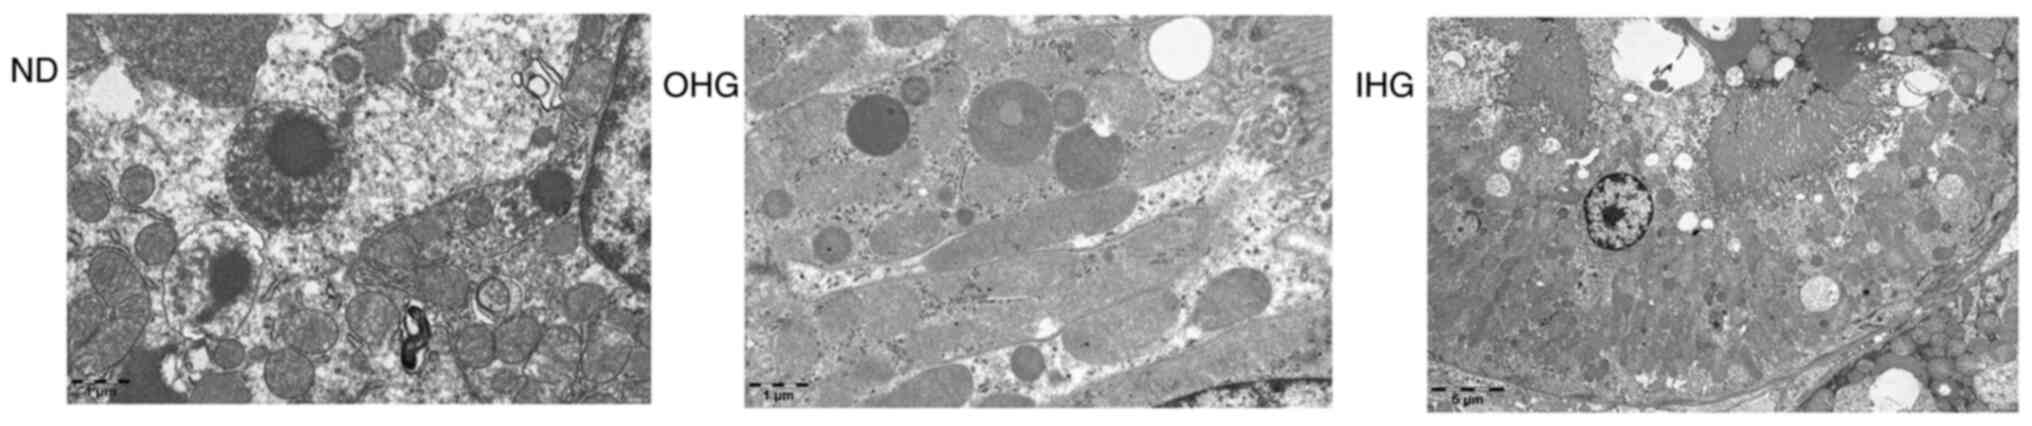

Following observation under an optical microscope, no obvious pathological lesions were identified in the kidney and pancreatic tissues of the rats (Fig. 5). Following transmission electron microscopy, however, a degree of glomerular cell swelling was identified, the internal structure of mitochondria was found to be empty and mitochondria were disintegrated (Fig. 6).

Figure 6

Results of transmission electron microscopy. High glucose induced glomerular cell swelling. The internal structure of mitochondria became empty and mitochondria disintegrated. Magnification, x5,000.

Diabetic nephropathy (DN) is the leading cause of end-stage renal disease worldwide. Chronic hyperglycemia is the main risk factor for the development of DN (39,40). However, the time of DN onset remains unclear and clinical studies have yet to provide a conclusive answer. In the present study, no obvious pathological lesions were identified in the kidney tissues of the rats. However, glomerular cell swelling and mitochondria disintegration were identified, using transmission electron microscopy, after 2 weeks of high glucose intake. Apoptosis of glomerular cells was increased to a certain degree in the present study. This suggests that formation of glycotoxins in renal cells occurred quickly, however, further research is required to confirm this.